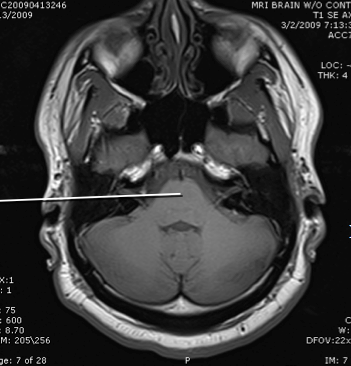

tegmentum of the pons

basis of the pons